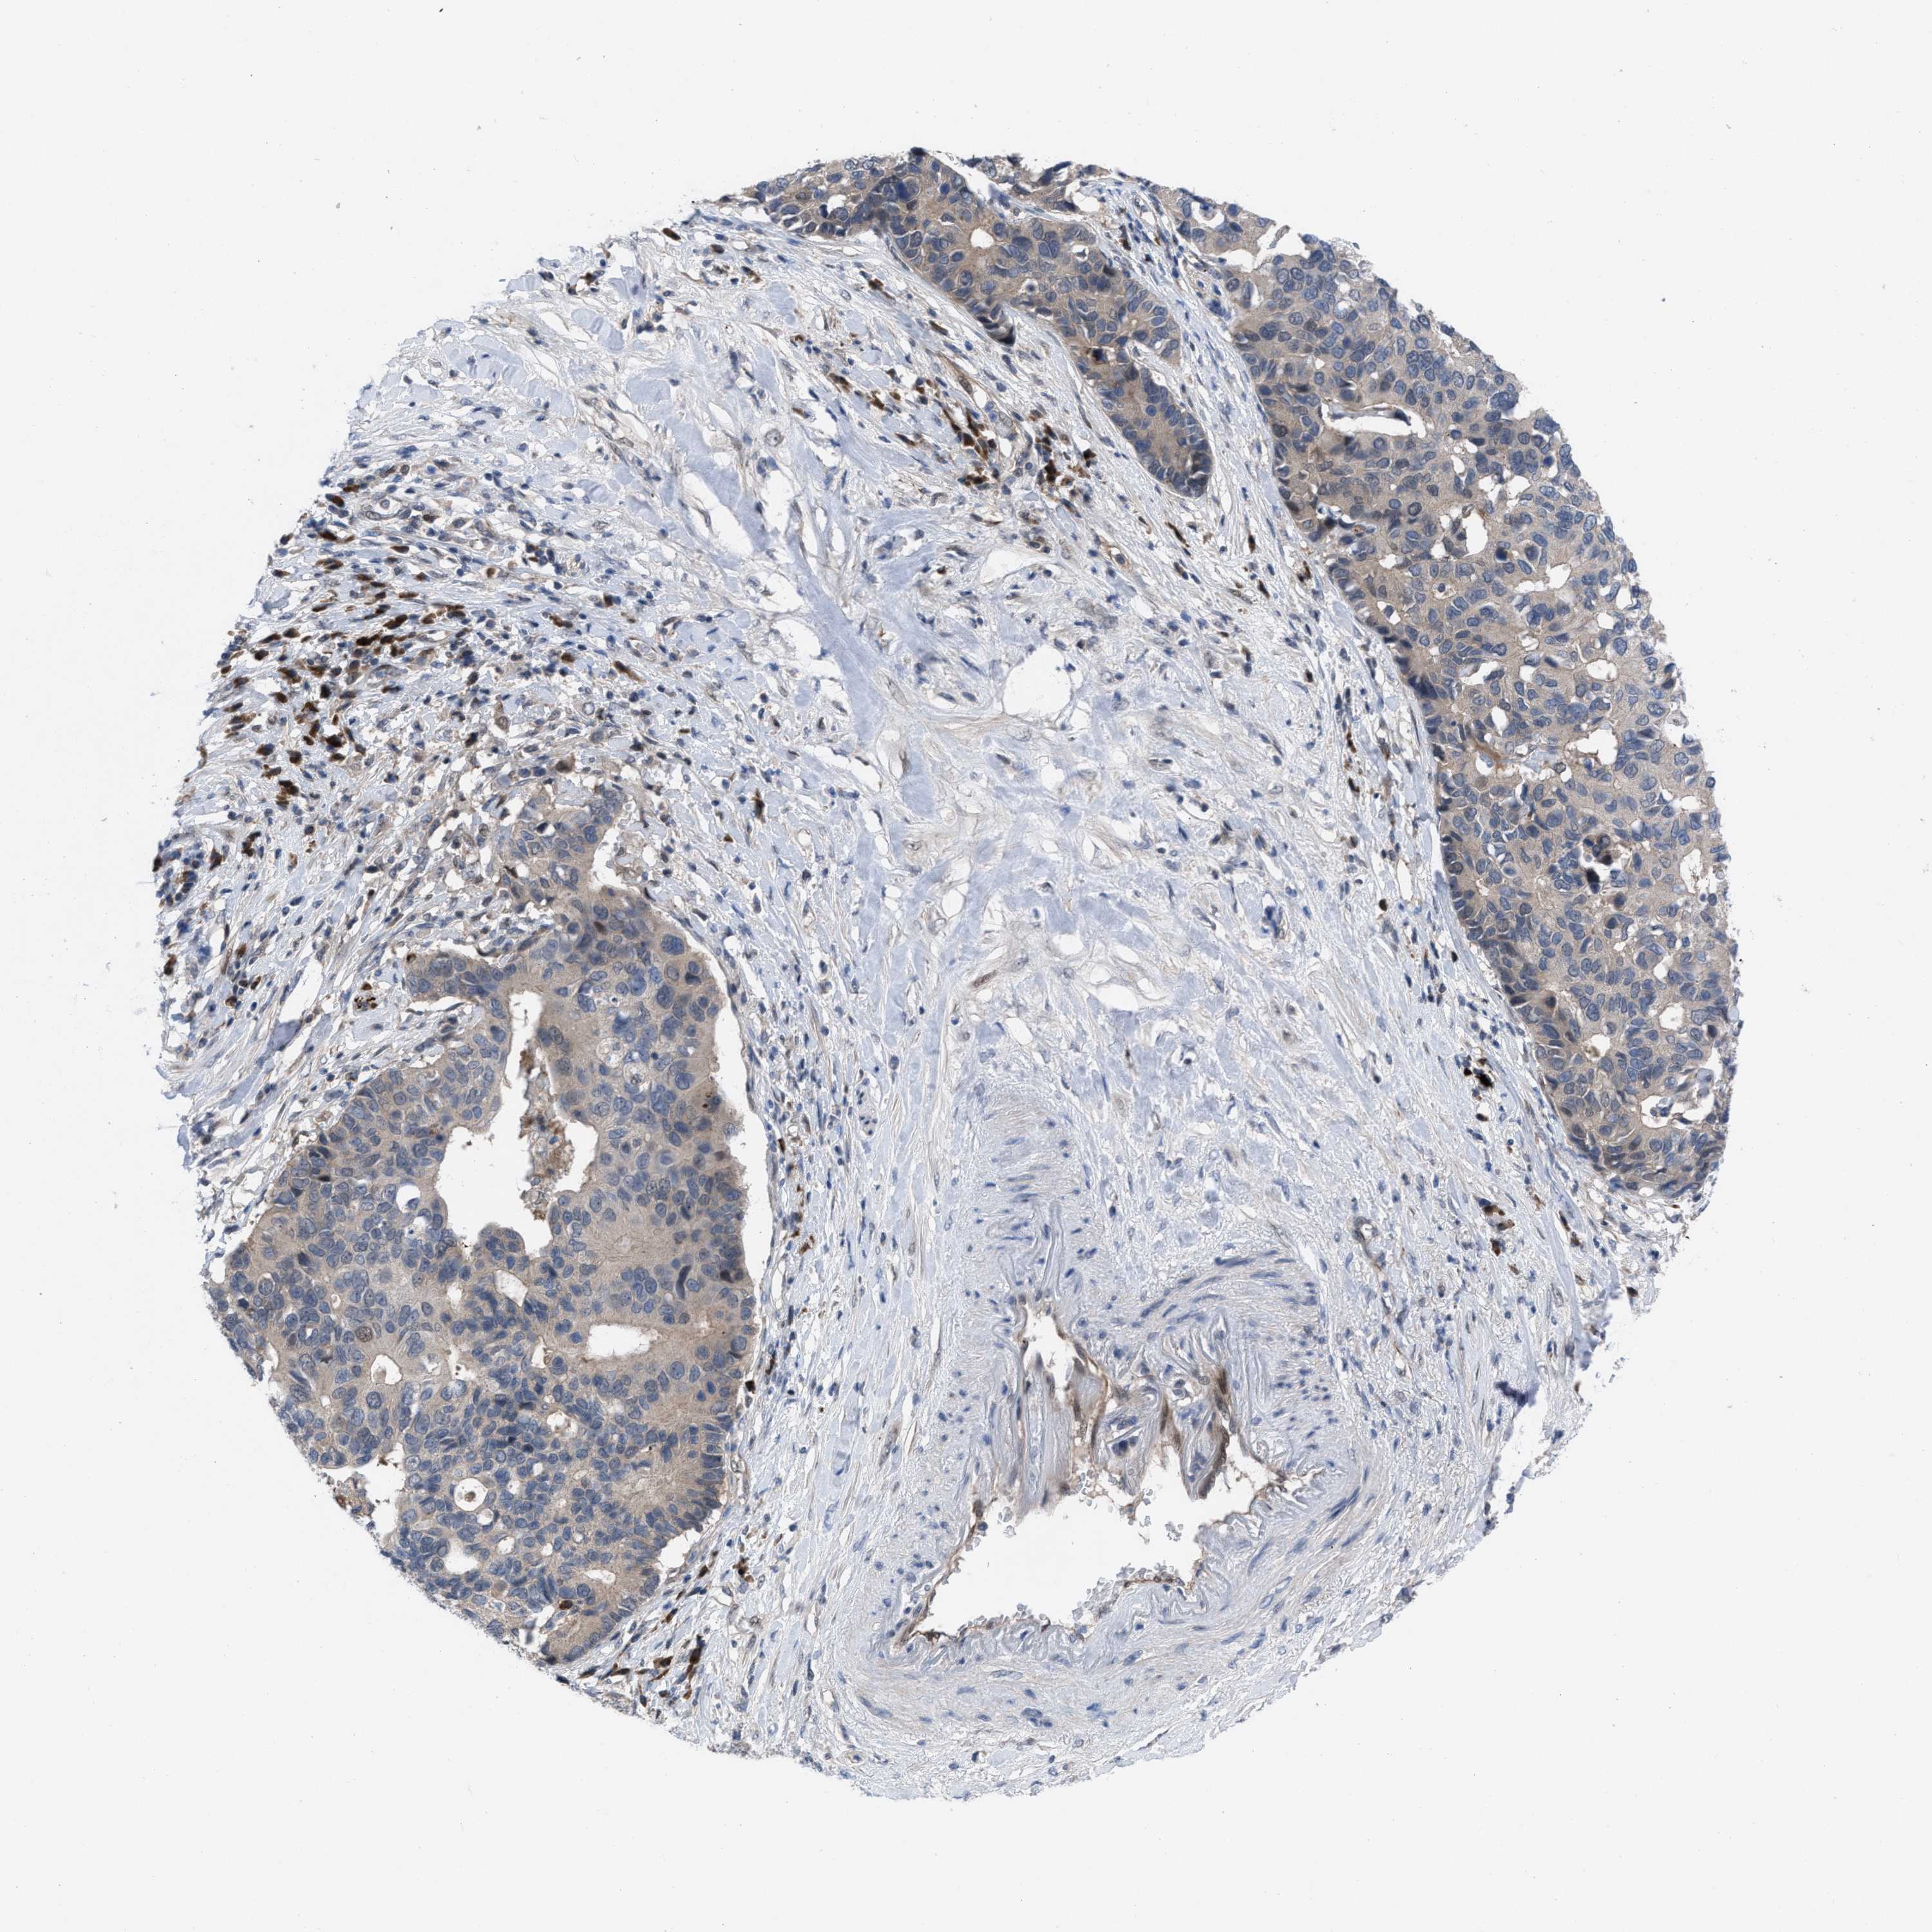

PANCREATIC CANCER - Protein expressioni

A mouse-over function shows sample information and annotation data. Click on an image to view it in a full screen mode. Samples can be filtered based on level of antibody staining by selecting one or several of the following categories: high, medium, low and not detected. The assay and annotation is described here.

Note that samples used for immunohistochemistry by the Human Protein Atlas do not correspond to samples in the TCGA dataset.

Antibody stainingi

Antibody staining in the annotated cell types in the current human tissue is reported as not detected, low, medium, or high, based on conventional immunohistochemistry profiling in selected tissues. This score is based on the combination of the staining intensity and fraction of stained cells.

Each image is clickable and will lead to virtual microscopy that enables deeper exploration of all samples and also displays staining intensity scores, fraction scores and subcellular localization as well as patient and tissue information for each sample.

Antibody HPA019011

Staining

High

Medium

Low

Not detected

Intensity

Strong

Moderate

Weak

Negative

Quantity

>75%

75%-25%

<25%

None

Location

Nuclear

Cytoplasmic/membranous

Cytoplasmic/membranous,nuclear

Adenocarcinoma, NOS